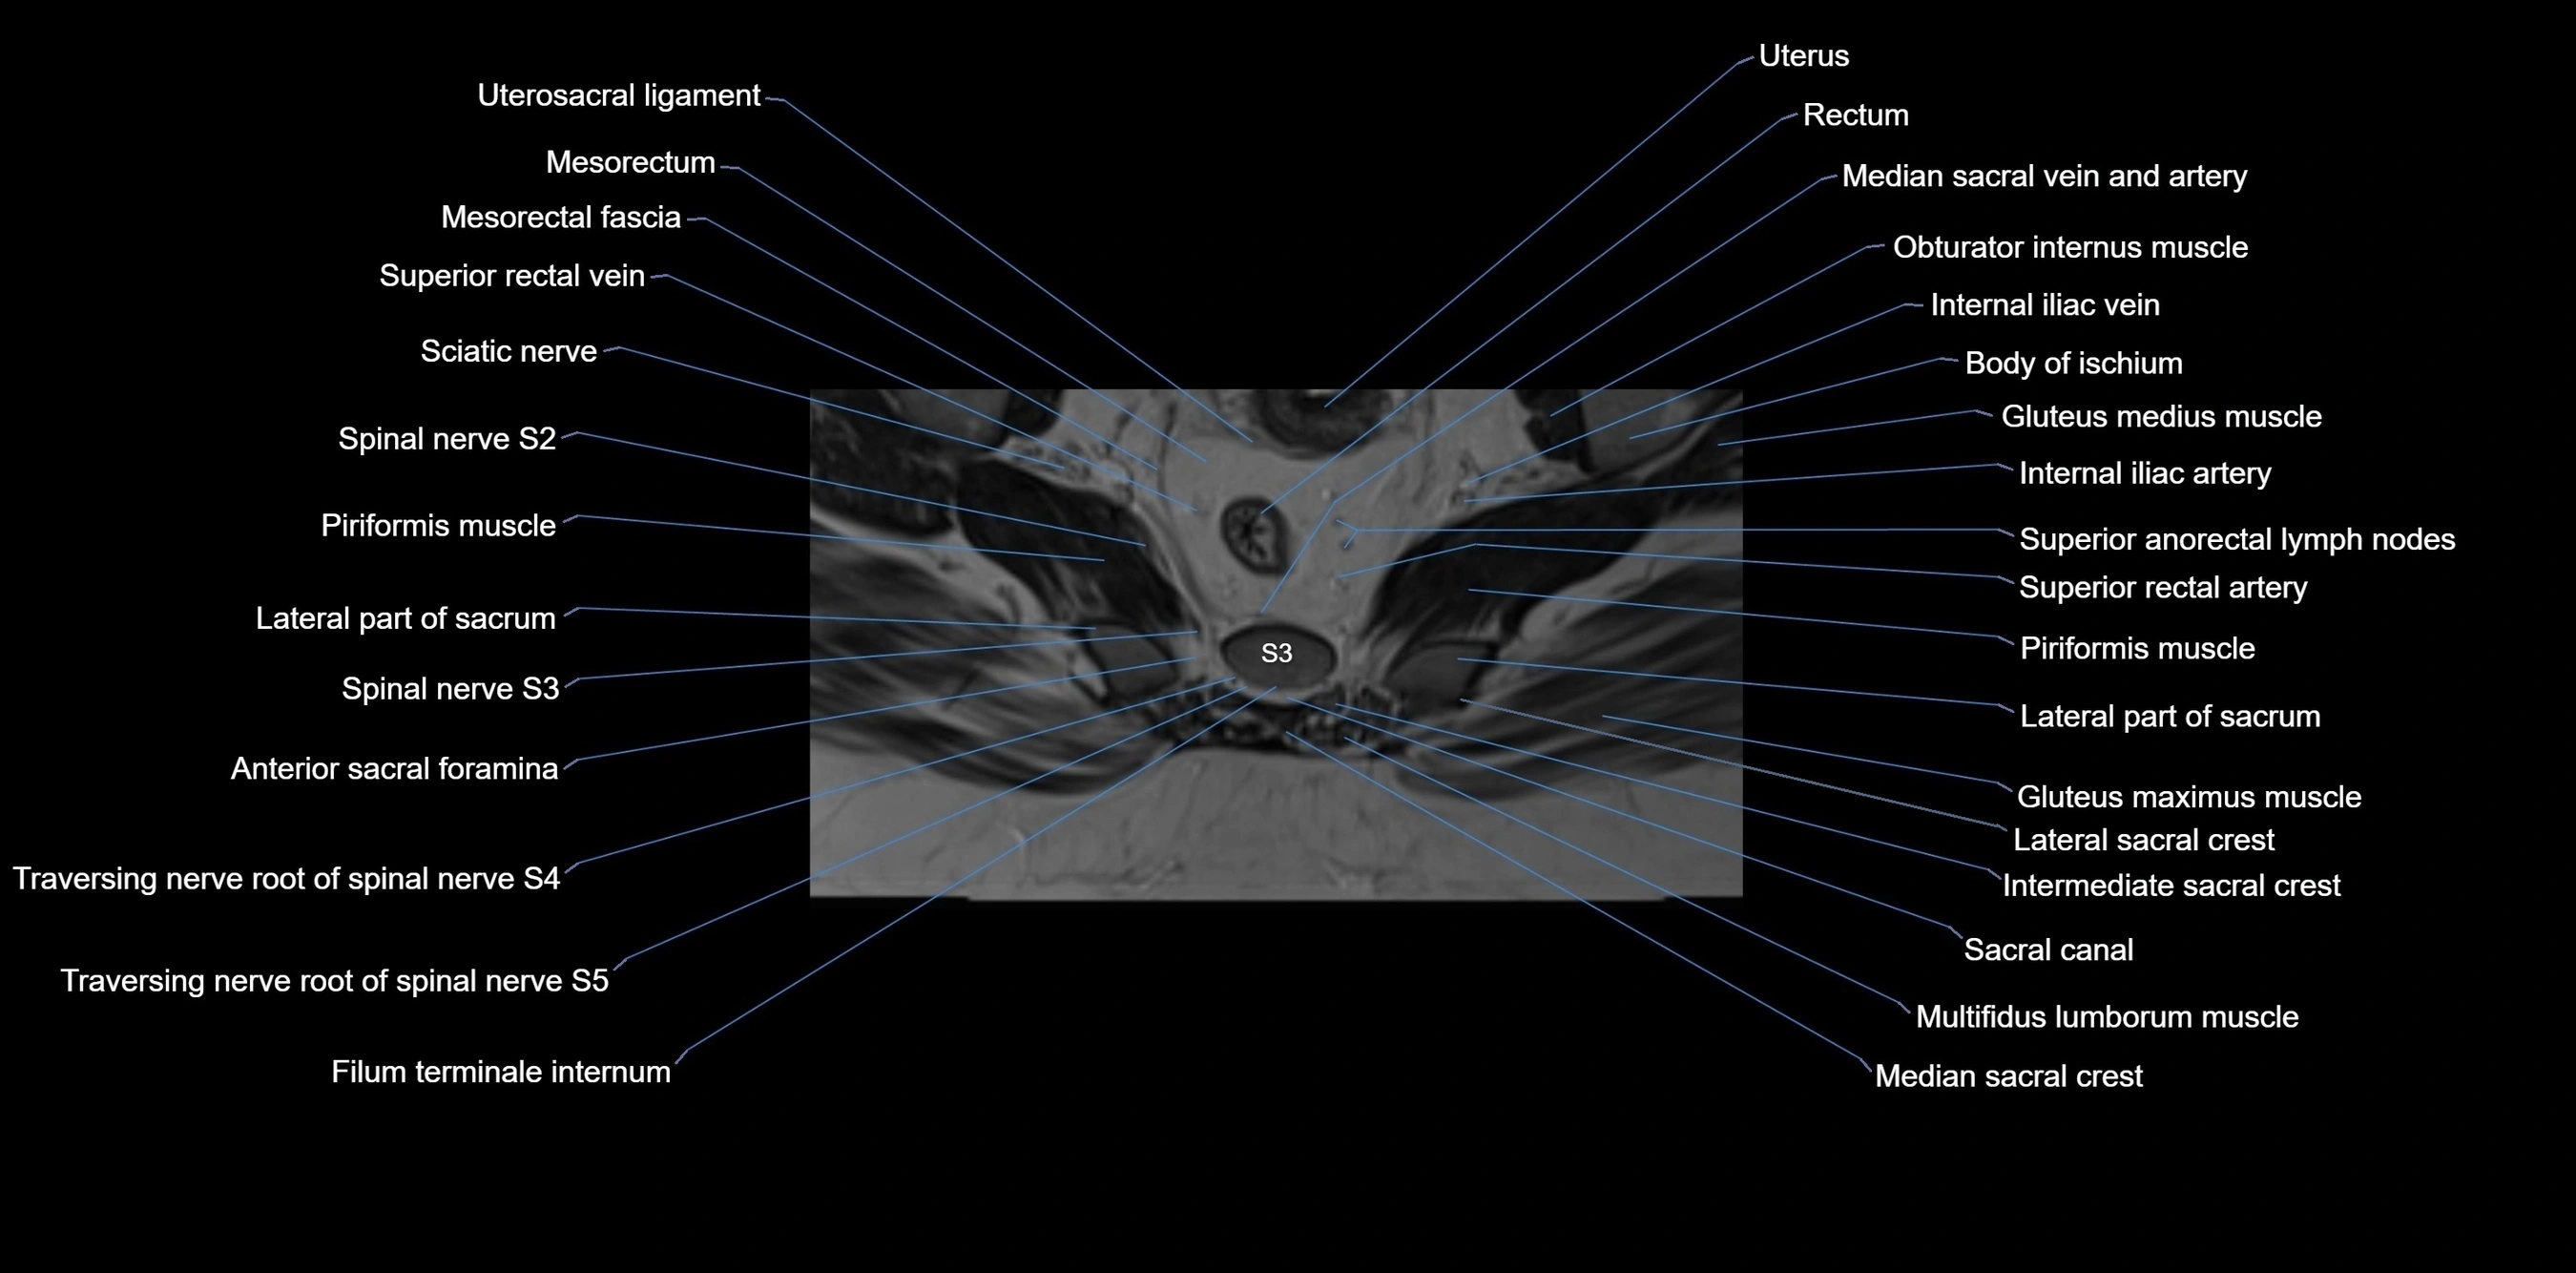

CT VRT image

image